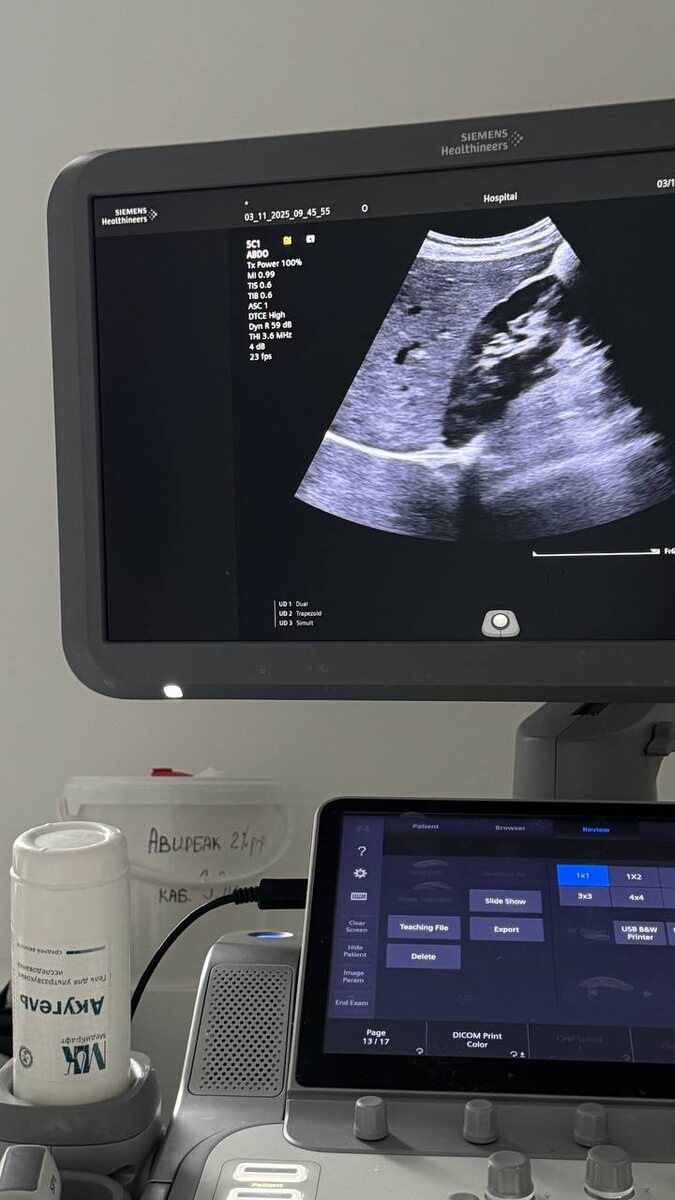

Резко поплохело печени

Резко поплохело печени.